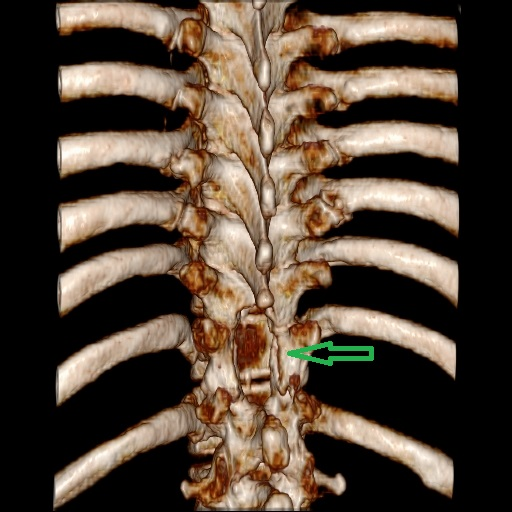

患者康婆婆(化名)今年已近70岁,因“右下肢麻木5+月加重伴疼痛3+月”前来医院治疗,行腰部核磁检查发现胸11椎体平面脊髓内囊性占位,考虑室管膜瘤的肿瘤性病变。患者下肢长期麻木伴疼痛,经神经外科医疗团队研究讨论,为患者行了微创的胸椎椎管骨质切开和脊髓内肿瘤病变的切除手术治疗,切除了患者的肿瘤后,患者下肢肌力和麻木感明显改善。

手术前检查

术后手术图片